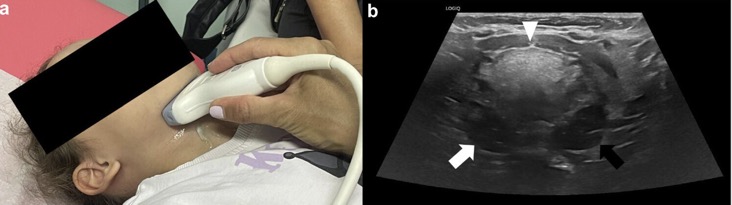

Pathologie tonsillaire: US

PATHOLOGIES INFLAMMATOIRES

EX: LYMPHOME DE BURKITT